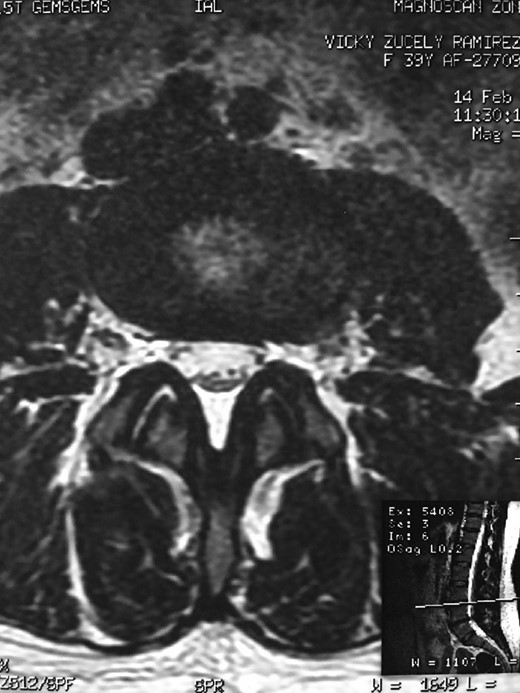

A 42-year-old female presented to the clinic with a history of chronic low back pain. She reported no relevant medical history. She had already been treated in the last 4 years by general practitioners with analgesics and home based physiotherapy with no satisfactory results. She had two previous admissions to the emergency department where morphine was prescribed to control the pain on her lower back. She was under ambulatory treatment with diclofenac, and tizanidine with partial relief of symptoms. Her main complaint was pain on the lower lumbar back with no radiation to the lower extremities. In her physical evaluation she presented limitation to full rotation and bending of the lumbar spine due to pain. Lasegue sign was negative, sensitivity, reflexes, sagittal balance, distal muscular strength and pulses were normal. Radiographs showed an overdeveloped left transverse process of the fifth lumbar vertebra which contacts with the sacrum at the left sacral wing with signs of degeneration at the same site (Fig. 1). Magnetic resonance imaging (MRI) studies were obtained (Figs 2–5). The patient was taken to the operating room where infiltration with 1 mL of lidocaine and 40 mg of Triamcinolone was performed in the pseudoarticulation between the left transverse process and the sacrum under fluoroscopic guidance. She reported a complete relief of pain after the procedure. At three months follow-up she was managed with strengthening and stabilizing exercises for the lumbar spine and postural education was initiated. She remains asymptomatic at her 12 months follow up.

RMN of the patient showing smaller facets in the anomalous articulation and healthy disc compared to the supradjacent one (next figure).

The partial fusion at the lower part of the lumbosacral transition produces important alterations in normal biomechanics at the levels immediately above and below the LSTV. Changes such as hypermobility and abnormal torque moments are present at the level above the LSTV, predisposing it to early degeneration (early disc pathology and facet joint degenerative disease). Restricted movement below the LSTV produces a protective effect against degeneration of disc and facets and is related to changes (facets are smaller and coronally oriented) in the dimensions of the lower level facet joints [7]. These alterations can be verified in the adjacent levels of the LSTV in our patient.